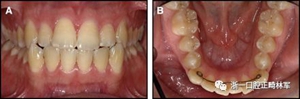

圖5.尖牙到尖牙的弓絲仍然固定在兩端,拱形偏斜和尖牙相反方向的扭矩:A,正面視圖; B,咬合面視圖(Rick Booth博士提供)。

圖6.尖牙到尖牙弓絲在切牙處向下偏斜(可能來自咬合力),導致通過尖牙的擴張:A,正面視圖; B,咬合面視圖。